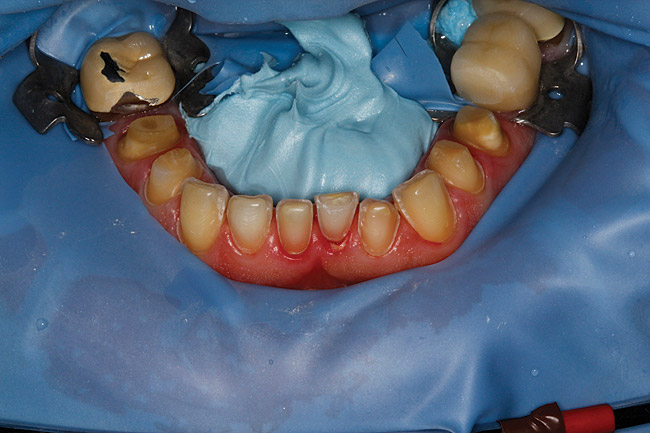

Figure 34  After isolating the preparations from moisture using a latex-free rubber dam and blue mouse, the restorations were ready to be inserted.

Figure 34

Figure 35  The mandibular IPS e.max restorations were bonded in.